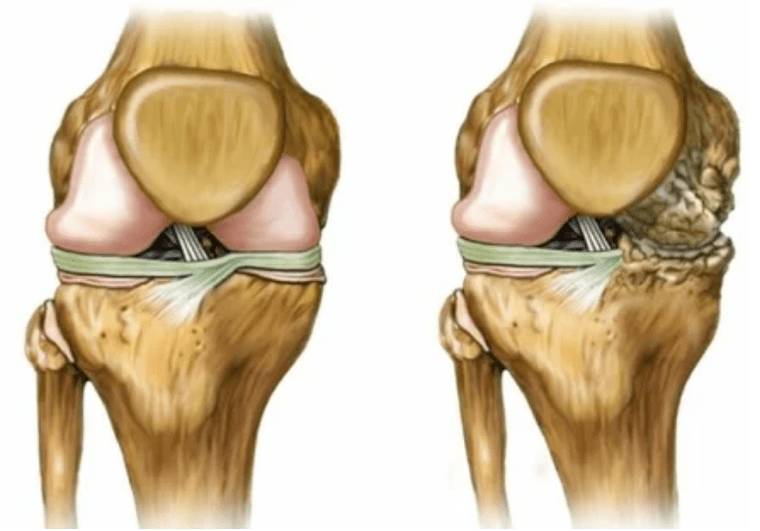

Articulation arthrosis develops for a long time, initially affects only hyaline cartilage, then spreads to bones, involves the synovial shell, the muscles and the entire joint capsule.In the first or early stage of arthrosis, the lesion manifests slightly: small pain after hard work, swelling, redness of the skin.Due to the ignoring uncomfortable sensations, the joint is deformed, inflamed, brings intense pain, its peak falls in the morning.The disease is characterized by the disappearance of pain after the development of the joint.If not treated, a person completely loses the mobility of the joint.

- Reducing the gap in the joint gap, which becomes noticeable in the image.The violation stage is determined by the diagnosis-tanthenologist.The patient feels the complexity or inability to completely straighten and double the limb;

- Articular deformation, the cartilage acquires an irregular shape, causing curvature;

- 3 degrees.Often, there is pain, it is difficult to move the limb due to changes in the joint.The lesions are extensive, become noticeable to the naked look.The deformation of the joint site occurs, the affected area swell and turns red.The limb axis is disturbed, which leads to the complexity of movement.Pathological changes cause ligament shortening.Subluta and contractures appear.Adjacent muscles are reduced or stretched, of which the contractive function is weakened.